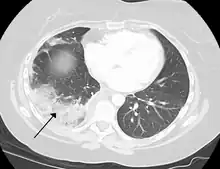

Because of the dual blood supply to the lungs from both the bronchial and the pulmonary circulation, this tissue is more resistant to infarction. An occlusion of the bronchial circulation does not cause infarction, but it can still occur in pulmonary embolism when the pulmonary circulation is blocked and the bronchial circulation cannot fully compensate for it.[2]